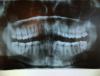

Baojia73 Опубликовано 19 апреля, 2013 Поделиться Опубликовано 19 апреля, 2013 Проконсультируйте, пожалуйста по снимку Ссылка на комментарий

IvanK Опубликовано 19 апреля, 2013 Поделиться Опубликовано 19 апреля, 2013 Консультация ОртодонтаЛечение:26,36,37,46...КТ - для просмотра пазухОчень рекомендую сходить к гигиенисту, пользоваться зубной нитью. Ссылка на комментарий

Baojia73 Опубликовано 19 апреля, 2013 Автор Поделиться Опубликовано 19 апреля, 2013 а можно поподробнее что в 26,36,37?в 46 насколько я понимаю большая полость? Ссылка на комментарий

IvanK Опубликовано 19 апреля, 2013 Поделиться Опубликовано 19 апреля, 2013 а можно поподробнее что в 26,36,37?в 46 насколько я понимаю большая полость?Подробнее можно сказать только при очной консультации у врача-стоматолога терапевта. Ссылка на комментарий